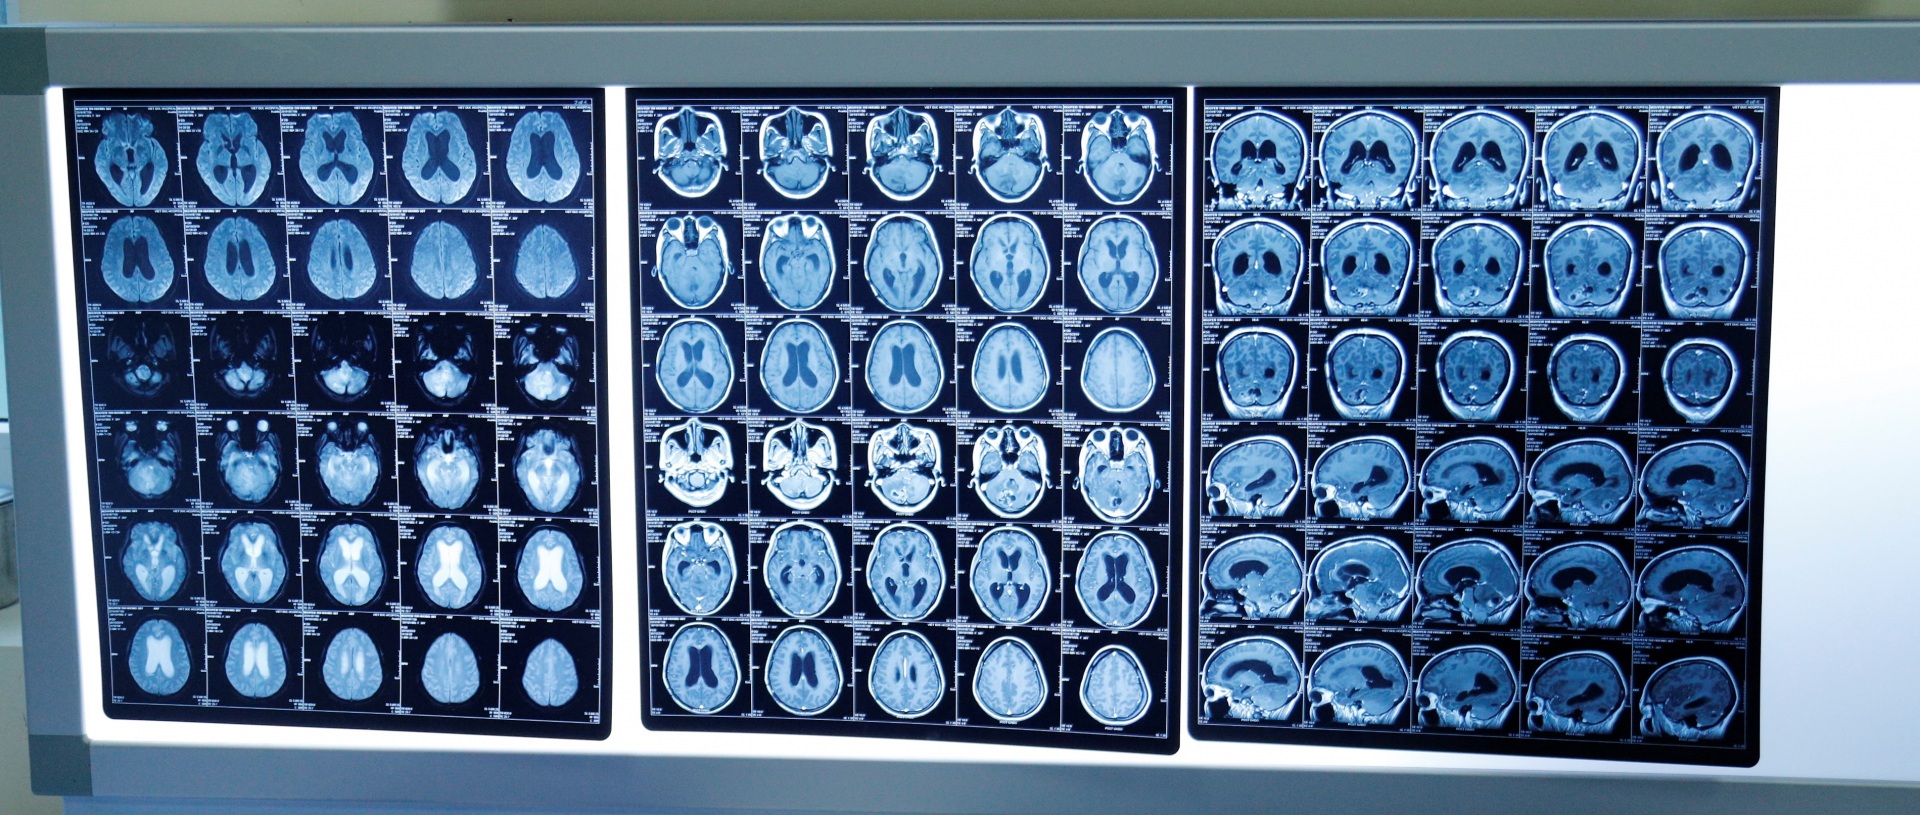

Hình ảnh khối u di căn não chị H.

Chị H. vui mừng chờ đợi giây phút được làm mẹ nhưng đến tuần 28 khối u phát triển di căn não. Giữa nguy hiểm cận kề, chị vẫn quyết tâm giữ lại sinh linh bé bỏng đang mang trong mình - đứa trẻ mà chị hy vọng, ngóng chờ nhiều năm qua dù biết phải đánh đổi cả sinh mệnh của mình.

Bác sĩ xác định, bệnh nhân H. được đánh giá là trường hợp đặc biệt với tổn thương ở phía hố sau cạnh các cấu trúc và kích thước tương đối lớn, nếu xạ phẫu 1 lần duy nhất thì trong tình trạng hôn mê, sức khoẻ bệnh nhân sẽ không đảm bảo. Do đó các bác sĩ quyết định xây dựng kế hoạch điều trị chia làm 3 phân liều cách nhau 2 tuần.

Tiếp nhận trường hợp chị H. sau sinh, TS.BS Nguyễn Đức Liên, Trưởng khoa Ngoại thần kinh Bệnh viện K cho biết,đây là trường hợp rất đặc biệt, sản phụ sau sinh được 3 ngày, phải chuyển khẩn cấp sang Bệnh viện K do ung thư vú di căn não. Khi vào viện khối u đã di căn vào não 3 ổ, đặc biệt di căn vào hố sau gây chèn ép, dẫn đến tình trạng hôn mê, chúng tối ngay lập tức quyết định điều trị bằng thuốc và điều trị bằng dao Gamma cho bệnh nhân H.

Theo bác sĩ Liên, khó khăn lớn nhất là phải cân nhắc giữa phẫu thuật mở thông thường và xạ phẫu Gamma Knife, do khối u khá lớn, vị trí 2 khối ở tiểu não, 1 khối ở bán cầu đại não, cả 3 khối cộng vào gây ra triệu chứng cộng hưởng.

“Chúng tôi phải hội chẩn với bác sĩ chuyên khoa về ung bướu thần kinh và u vú, đưa ra phác đồ điều trị phối hợp cùng nhau giúp bệnh nhân hồi phục, vì nếu chỉ tập trung vào điều trị u não thì có thể di căn bộ phận khác, nếu chỉ điều trị bệnh toàn thân thì có thể hôn mê, cơ thể không chịu được. Vì vậy, phải phối hợp nhịp nhàng, điều trị não trước, nếu mổ mở có thể chỉ giải quyết được 1 ổ, dao Gamma có thể giải quyết cùng một lúc cả 3 ổ, khối u được khống chế, giảm được thời gian hồi phục 2-3 tuần nếu mổ mở thông thường, tuy nhiên các phương án đều được cân nhắc”, TS. Liên đánh giá.

Hiện tại sức khoẻ hai mẹ con chị H. đã ổn định, mẹ tiếp tục được theo dõi, điều trị. Điều kỳ diệu đã đến với mẹ con chị H. sau bao nỗ lực của ekip các bác sĩ Bệnh viện K và nghị lực của chị. Sau khi điều trị với phác đồ bằng dao Gamma 2 ngày chị đã dần phục hồi trí nhớ, tỉnh táo trở lại. Sau 6 tuần điều trị, bệnh nhân H. đáp ứng thuốc rất tốt, khối u đã giảm 40% thể tích, và được kiểm soát tốt, bên cạnh đó việc phối hợp với điều trị hóa trị đã giúp kiểm soát bệnh rất tốt.